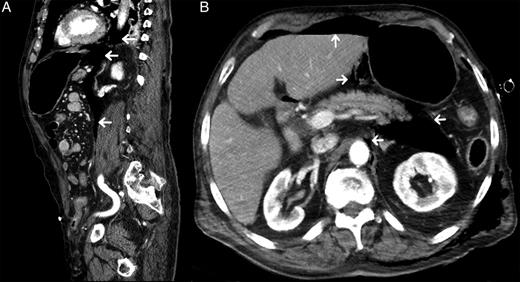

An 82-year-old male with past medical history of diabetes mellitus and alcohol abuse arrived by ambulance after being found unresponsive at the bottom of a flight of stairs with a scalp laceration. While en route to the hospital, two unsuccessful intubation attempts were made for a Glasgow coma scale (GCS) of 8. Upon arrival in the emergency department (ED), his GCS was determined to be 3 and was intubated with use of the Glidescope. Physical examination revealed decreased breath sounds on the left and crepitus over the left chest wall, suggestive of subcutaneous emphysema, and an immediate tube thoracostomy was performed prior to chest X-ray (CXR) to reduce the suspected pneumothorax. CXR post chest tube placement demonstrated large amounts of subcutaneous emphysema (Fig. 1 ), which was also visible on computed tomography (CT) scan along with evidence of pneumomediastinum and pneumoperitoneum (Fig. 2), with pneumoretroperitoneum and pneumoperitoneum present on abdominal CT scan (Fig. 3). As a result of the fall, he also sustained a fracture of the right frontal bone, fractures of the C2 and C3 vertebrae, and mild subarachnoid and subdural hemorrhage without shift. There were no intra-abdominal injuries found. He was admitted to the surgical intensive care unit (SICU) and maintained on mechanical ventilation, remaining hypotensive, hypothermic and mildly tachypneic, becoming increasingly unstable over the next 8 h. Due to the known pneumomediastinum, pneumoperitoneum and worsening instability, he was taken to the operating room for suspected viscus perforation and peritonitis. An exploratory laparotomy was performed, which revealed air within the lesser sac, but no evidence of bleeding or perforation. When closing the operative site, crepitus was also noted over the right chest wall, and a chest tube was placed into the right pleural space.

Sagittal view from CT abdomen/pelvis with contrast (A) showing areas of free air in mediastinum and thoracic cavity spreading downward into peritoneum (white arrows). Coronal view (B) showing free air within the abdominal cavity. Pockets are visible around the aorta, pancreas and liver (white arrows), as well as the presence of subcutaneous emphysema.